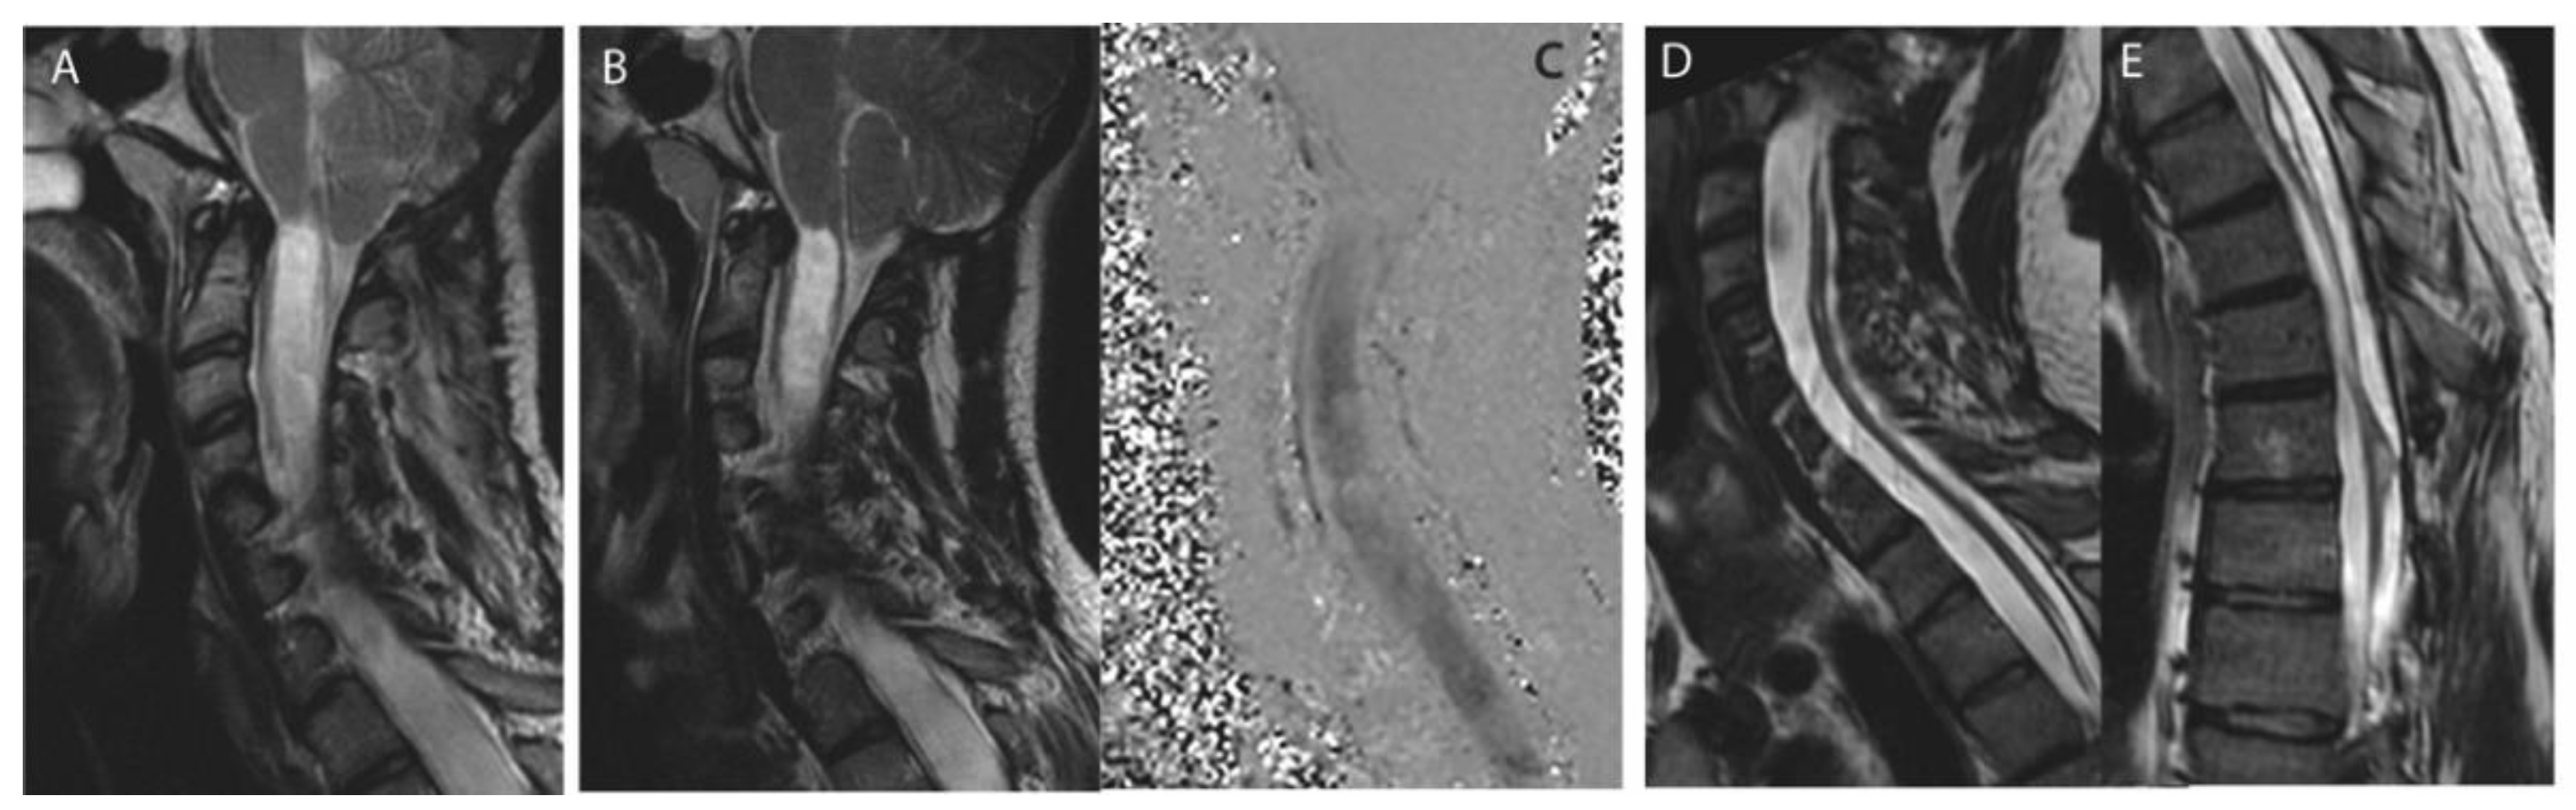

Figure 2. Craniovertebral junction revision after Chiari decompression failure. Case of a 39 years-old female patient initially operated on at another center for a Chiari I malformation without syringomyelia before index decompression surgery (A). Foraminal arachnoiditis and progressing syringomyelia (B), syringobulbia (C) and no CSF flow at the craniovertebral junction (D) 7 years postoperatively. CVJ revision was performed: bone decompression was enlarged, duraplasty was removed, and tonsilles were coagulated allowing resolution of the syringomyelia at 1 year postoperative (E).

Revision surgery was most frequently performed at the level of the foramen magnum (25/35, 71.4%, e.g., Figure 2) and consisted in performing or replacing the duraplasty (in all cases) in association with either foraminal arachnolysis (51.4%); additional bone decompression (37.1%), tonsillectomy or tonsillar coagulation (25.7%), 4th ventricle to cervical subarachnoid spaces shunt (5.7%). Foraminal arachnoiditis was noted in 51.4% of cases (Table 2).